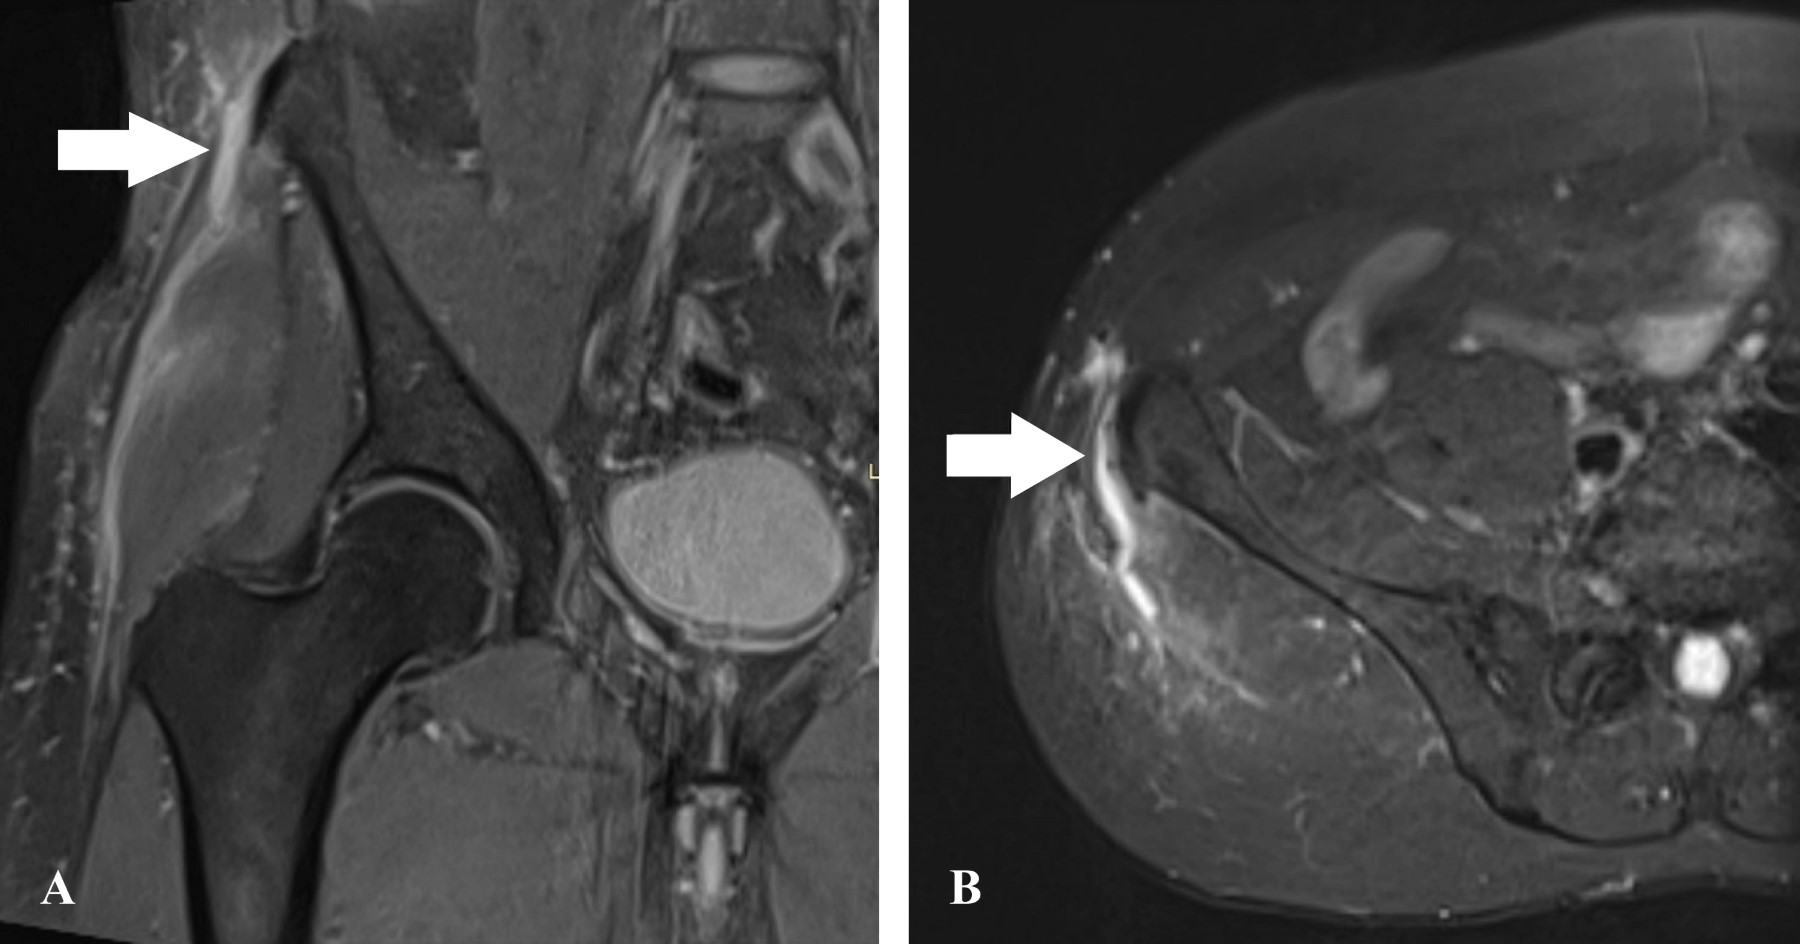

El paciente se había sometido a cirugías por un desgarro del ligamento cruzado anterior en la rodilla derecha hace 27 años y por un desgarro del menisco medial en la rodilla izquierda hace 19 años. Al examen físico, se observó edema leve en la región lateral de la cadera, sin hematomas. Las pruebas de fuerza revelaron dolor en la cadera derecha y disminución de la fuerza en comparación con la cadera izquierda. Los resultados de la resonancia magnética confirmaron un desgarro completo de la inserción proximal de la banda iliotibial (Figura 1).

Las pruebas de imagen, en particular la resonancia magnética, son esenciales para el diagnóstico, ya que la radiografía y la tomografía computarizada pueden mostrar cambios sutiles o dar resultados negativos. La resonancia magnética permite visualizar los desgarros de la banda iliotibial y sus extensiones, ya sea en sus inserciones ilíacas o a nivel del trocánter mayor. Además, la resonancia magnética puede revelar áreas hinchadas, acumulación de líquido y discontinuidad de las partes afectadas.1

Figura 1